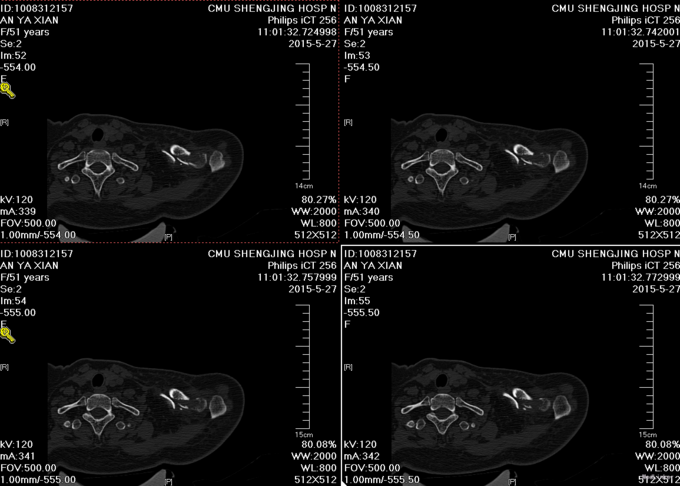

主诉:摔伤后左肩部疼痛活动受限18天 现病史:患者自述于2015-5-9日中午在沈阳市辽岛附近骑直行车时自己摔伤,左肩部着地,伤后患者左上肢疼痛活动受限,急诊送至沈阳市胸科医院,行左肩关节正位DR,提示为左锁骨骨折,患者于胸科医院保守治疗肋骨骨折13天,于2015-5-22日出院,现患者感觉左肩部疼痛,为求进一步治疗来到中国医科大学附属盛京医院创伤骨科,患者入科后神志清楚,饮食佳,无头晕头迷,无恶心呕吐,二便正常。

专科查体:患者左上肢吊臂带悬吊中,左肩关节肿胀,可见锁骨隆起,压痛(+),叩击痛(+),锁骨远端按压有浮动感,左上肢感觉正常,桡动脉搏动有力,末梢血运良